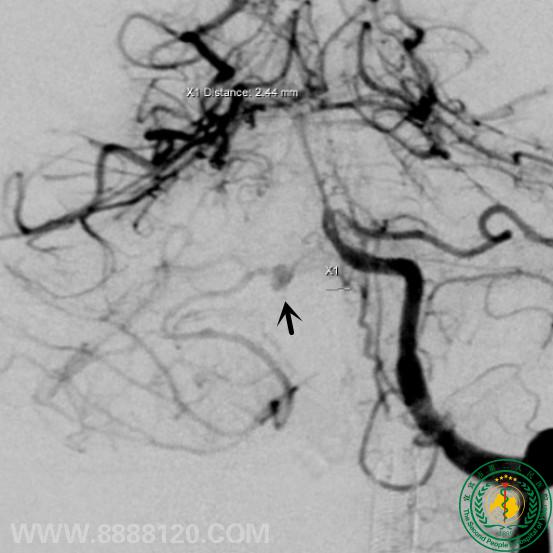

头颅CTA示右侧小脑前下动脉动脉瘤,DSA证实。

采用弹簧圈填塞、注胶技术治疗后,显示动脉瘤无显影。